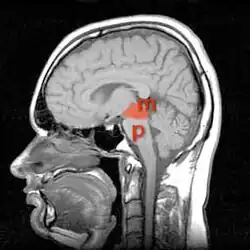

Причиной развития синдрома является поражение в области моста мозга или среднего мозга[1]. Поражение этой области может развиваться вследствие инфаркта мозга, кровоизлияния в мозг, нервно-мышечных и демиелинизирующих заболеваний (Например: центральный понтинный миелинолиз), травмы[6], опухоли[7], инфекционного поражения.[8][9]

Средний мозг на МРТ (отмечен красным), а мост буквой Р(pons)

Наиболее часто при синдроме запертого человека происходит повреждение ствола мозга в области передних отделов моста или среднего мозга. В этом регионе проходят: кортикоспинальный тракт иннервирующий мышцы конечностей, кортико-бульбарный путь к ядрам черепных нервов (тройничный нерв, лицевой нерв, языко-глоточный, блуждающий, добавочный и подъязычный нервы). Этим объясняется наличие в клинической картине паралича конечностей (поражение кортико-спинального пути), нарушение речи и глотания и мимики (поражение путей к черепным нервам). При этом пути проходящие в задних отделах остаются неповрежденными, так при сохранности ядер и путей глазодвигательного нерва возможны движения глаз по вертикали, также не нарушается слух. Ретикулярная формация, благодаря которой сохраняется сознание проходит в более задних отделах и не страдает. На основании сохранности тех или иных структур, создана классификация синдрома запертого человека.[23][8]